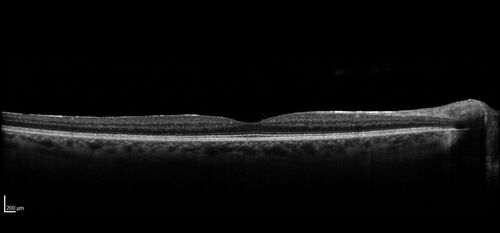

AZOOR - Inactive

Sudden vision loss in the left eye 3 years ago. Labs for syphilis, sarcoid and TB all negative. VA 20/32 OD, 20/80 OS